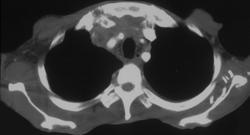

Pulmonary Embolism